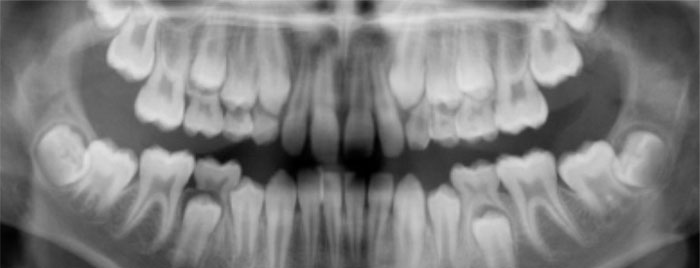

- Panoramic X-Ray is a single x-ray that manages to get all the upper and lower teeth, large portions of the jaws and other structures in one picture. This kind of x-ray does not provide as much detail as the x-rays that include smaller areas.

This panoramic x-ray shows baby teeth as well as the developing permanent teeth that have not yet reached the surface.